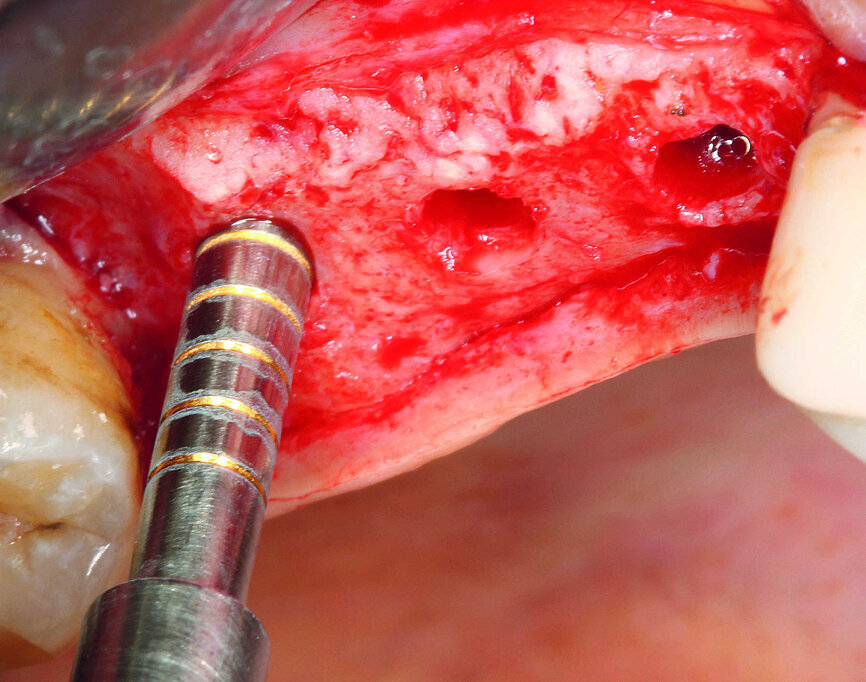

Avant le traitement chirurgical, les zones des deuxième et troisième quadrants ayant besoin d’être restaurées l’ont été au moyen d’éléments de bridge tout-céramique et dans le premier quadrant, la dent 14 a été recouverte par une couronne en disilicate de lithium produite par CAD/CAM. Une planification numérique a été utilisée pour déterminer l’orientation des implants en fonction des éléments prothétiques, afin d’obtenir la meilleure prédictibilité possible pour la réussite du traitement sur le plan clinique. Les données CBCT du scannage intraoral ont donc été superposées aux trois couronnes conçues numériquement (Fig. 3), puis les positions, les alignements axiaux et les longueurs des trois implants ont été déterminés à l’aide du logiciel de planification (Fig. 4). Étant donné qu’il n’existe encore aucune solution guidée pour le système implantaire utilisé pour ce cas, un gabarit d’orientation a été fabriqué au laboratoire d’après les données de planification rassemblées, reproduisant le bord anatomique et l’alignement des dents à remplacer. Le gabarit était précisément adapté aux dents adjacentes (Fig. 5). Implantation L’incision crestale a été réalisée après une anesthésie superficielle de la zone, suivie d’une anesthésie par infiltration. Elle a été pratiquée selon une direction légèrement palatine et s’est poursuivie par une incision paramarginale du côté vestibulaire autour de la dent 18. Aucune incision de décharge verticale localisée en distal n’a été réalisée, afin de ne pas diminuer l’apport sanguin dans les lambeaux. Après la préparation du lambeau mucopériosté, la position de l’implant a été marquée sur l’os au moyen du forêt triangulaire et du gabarit d’orientation. L’étape suivante a consisté à forer des trous de guidage jusqu’à une profondeur située légèrement sous le plancher du sinus maxillaire, car l’élévation sinusienne devait ensuite être réalisée par la technique de l’ostéotome. Les axes des trous de forage ont été vérifiés à l’aide d’indicateurs de direction et le site implantaire a été élargi selon le protocole chirurgical (Figs. 6–8).

C’est Tatum, en 1986, qui fut le premier à décrire la technique indirecte d’élévation du plancher sinusien par abord à travers des trous de forage, puis en 1998, Summers a modifié la méthode pour en faire la technique de l’ostéotome telle qu’on la connaît aujourd’hui.3–5 Un examen systématique de la littérature spécialisée a montré que cette approche est prédictible et a peu d’incidence sur les complications peropératoires et postopératoires.6 La fracture du plancher sinusien situé sous le fond des trous de forage a été effectuée à l‘aide d‘un ostéotome (Stoma) adapté au diamètre de forage implantaire (Fig. 9). Grâce à l’utilisation de la technologie Piezon et surtout de curettes angulées miniatures pour sinus, la membrane de Schneider a été constamment maintenue en contact avec l’os et soulevée délicatement sous contrôle visuel (microscope chirurgical). Une membrane de collagène (PARASORB, RESORBA) a été introduite à travers les trous de forage dans la région dentaire 16–17, puis soigneusement appliquée sur le site implantaire, afin de prévenir une perforation de la membrane de Schneider (Figs. 10 et 11). Le filetage a été taraudé pour éviter une surchauffe de l’os pendant l’insertion des implants en zircone dont la conductivité thermique est inférieure à celle des implants en titane (Fig. 12). Des implants (CERALOG Hexalobe, CAMLOG) de 8 mm de long ont été insérés avec un couple de serrage maximal de 35 Ncm contrôlé manuellement, et une vitesse de rotation maximale de 15 tr/min (Fig. 13). Le modèle de connexion du dispositif d’insertion était parfaitement adapté à la zircone. Ce dispositif permet une transmission radiale des forces et il est équipé d’un élément de rupture prédéfini, qui protège contre l’application d’un couple de serrage excessif, et donc contre une pression trop importante susceptible de provoquer des fractures de l’implant ou une nécrose de l’os (Tableau 2).

Les points de suture ont été retirés au cours de la visite de contrôle deux semaines plus tard, la plaie était bien cicatrisée et ne présentait aucune irritation. Après six mois, le patient est revenu pour le désenfouissement des implants. Une incision punctiforme a été pratiquée pour exposer les implants des régions dentaires 15 et 16, les coiffes de protection ont été retirées et des façonneurs gingivaux en PEEK ont été vissés au moyen d’une vis polyvalente, afin de modeler la gencive. Le tissu mou périimplantaire de la région dentaire 17 a été épaissi en phase préprothétique, par la préparation d’un lambeau muqueux qui a été transposé en direction vestibulaire. Ce modelage avec un façonneur gingival de 2,5 mm de haut a également été réalisé sans aucune suture supplémentaire (Fig. 18).